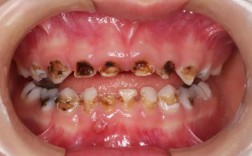

技术层面,主任需全面掌握各类矫治技术,包括传统金属托槽矫治、陶瓷托槽矫治、自锁托槽矫治、隐形矫治(如Invisalign、时代天使等)以及功能性矫治(如FRⅢ、Twin Block等),尤其擅长处理复杂病例,如骨性错颌畸形(III类骨面型、开颌等)、唇腭裂术后正畸、成人严重牙周病联合正畸治疗等,随着数字化正畸的普及,主任还需熟练运用口内扫描(如iTero、3Shape)、CBCT影像分析、计算机辅助设计(CAD)及3D打印等技术,实现精准诊断与个性化方案设计。

作为科室医疗质量的第一责任人,主任需建立完善的诊疗规范与质控体系,制定《正畸病例准入标准》《复杂病例多学科会诊制度》《矫治器消毒流程》等文件,定期开展病例讨论会(每月至少2次),对疑难病例进行集体会诊,确保治疗方案的科学性与安全性,在临床实践中,主任通常负责接诊转诊的复杂病例,如伴有颞下颌关节紊乱(TMD)的正畸患者、需要正畸-正颌联合治疗的重度骨性错颌患者等,其治疗方案直接影响患者的治疗效果与生活质量。

正畸中心主任在工作中面临多重挑战:病例复杂化(如成人患者伴随牙周病、颞下颌关节问题,需多学科协作)、患者需求多元化(部分患者追求“快速矫治”“隐形美观”,需平衡疗效与需求)、技术更新加速(数字化、智能化技术迭代周期缩短,需持续学习)、医疗风险管控(如矫治中牙根吸收、关节损伤等并发症的预防与处理)。